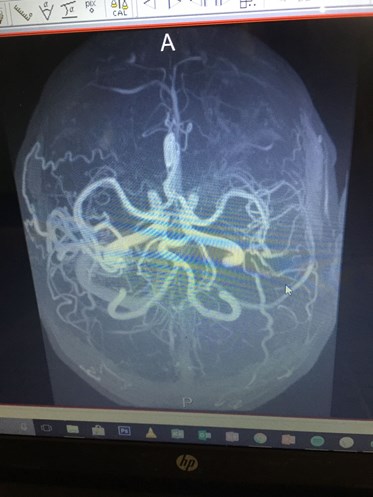

The Eden Park man was undergoing surgery for an arteriovenous malformation (AVM), often described as tangled blood vessels in the brain, when his stroke happened.